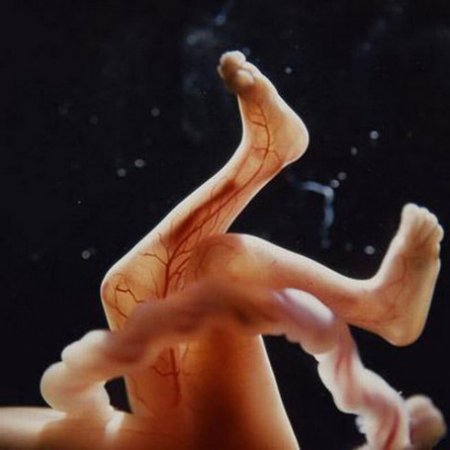

Пятая неделя беременности характеризуется формированием плаценты, являющейся источником кислорода и питательных веществ будущего человечка. Начинают формироваться уши и глаза ребёнка, появляются отростки пальчиков.

Длина эмбриона к концу пятой недели беременности составляет 6,5 мм. Также на этой неделе начинают формироваться зачатки сердечно-сосудистной системы ребнка, которые будут заканчивать свое развитие еще несколько недель